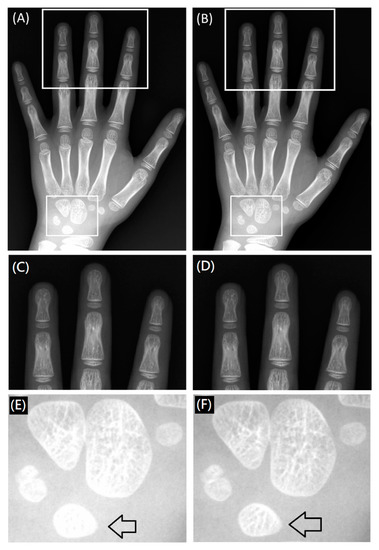

A posterior-anterior right-hand X-ray image (Figure 9) demonstrated inhomogeneous signal intensity in the anode-cathode direction due to the heel effect, where lower signal intensity (higher X-ray exposure) was noted in the finger than the wrist direction (Figure 9A,C,E). By applying the HEC, the inhomogeneity issue was minimized across the entire image, and small bony structures were more conspicuous in the corrected image than the raw image displayed with an identical window level and width (Figure 9B,D,F). Although the bony structures of the wrist in the raw image can be visualized by adjusting the window level and width, the bony structures of the fingers will be too dark to be visualized. This inhomogeneous issue can be reflected by the inconsistent nMI metrics in radial direction, as shown in Figure 8.

Figure 9. A posterior-anterior right-hand image acquired with 52 kVp and 10 mAs before (A,C,E) and after (B,D,F) HEC. The arrows indicate the bony structures of the lunate that were more conspicuous in the image with (F) than without (E) HEC.